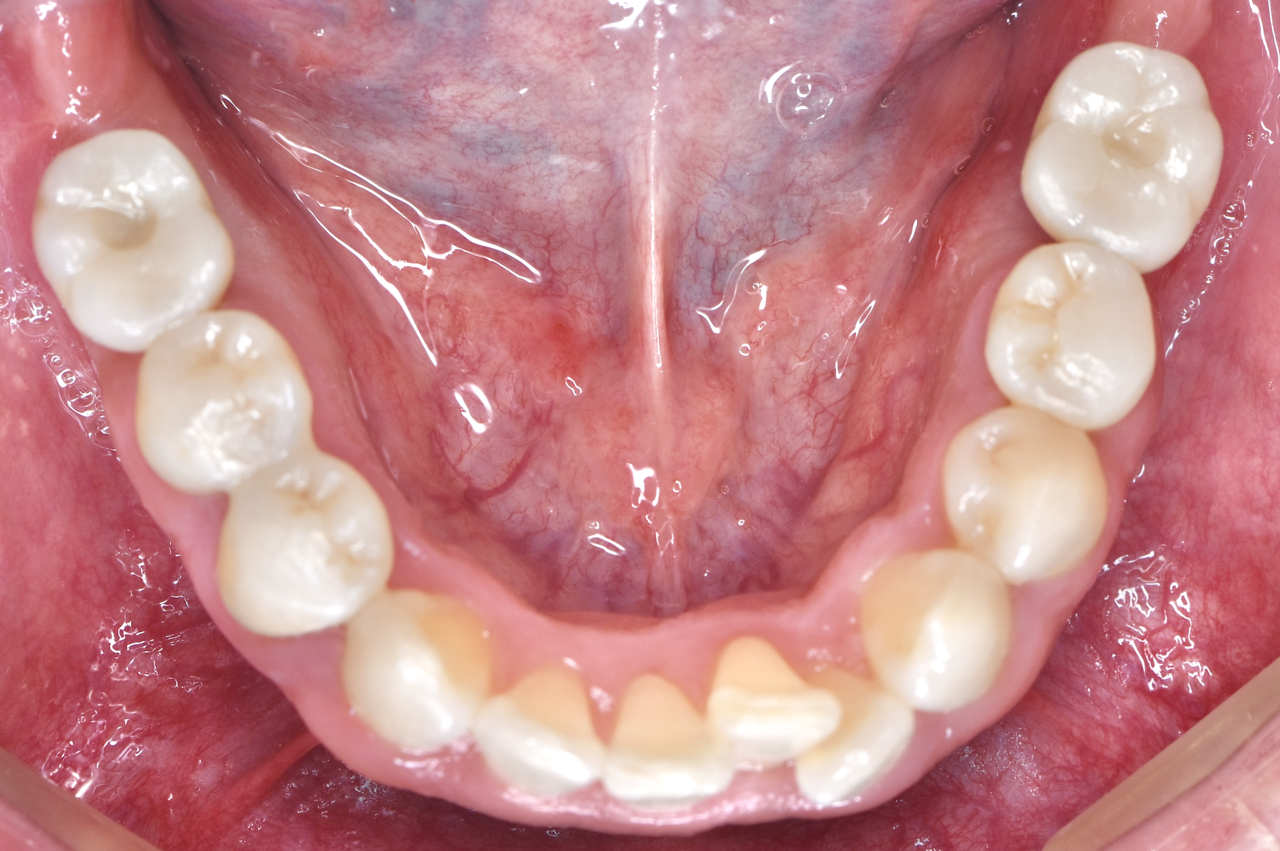

Before

20代 女性 失った歯をインプラントで復元

治療期間:約8ヶ月 費用約60万円

デメリット:費用が高い 外科処置が必要

After

根が割れて抜歯が必要になった部分に骨を補う処置

(リッジプリザベーション)を行い、骨が成熟するのを待ってインプラントを埋入しました